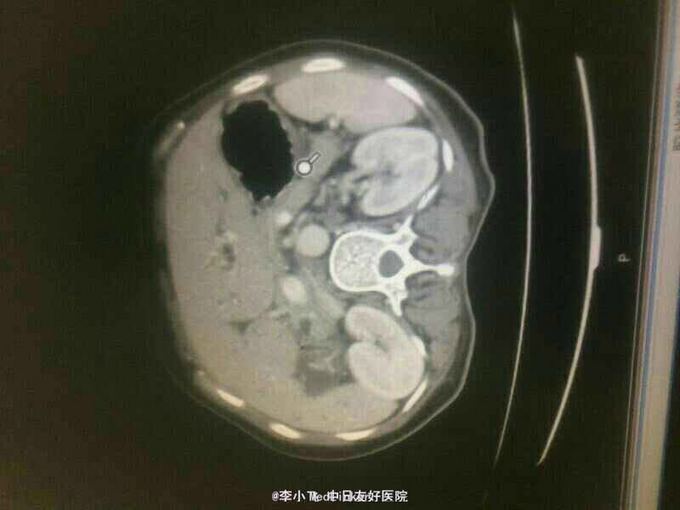

男性,50岁。右上腹胀痛半月,皮肤巩膜黄染10天入院 患者10天前进食后出现右上腹胀痛,平卧加重,伴后背放射痛,未重视。10天前出现皮肤巩膜黄染,就诊于当地医院,查腹部超声提示胆管扩张,胆管内占位性病变,为行进一步治疗入院。 既往史有高血压10年。血压控制可,余无特殊。

查体,生命体征平稳。右上腹压痛明显,剑突下轻压痛,无反跳痛。全腹未及明显包块。 腹部CT提示,肝内胆管扩张,肝外胆管内占位。